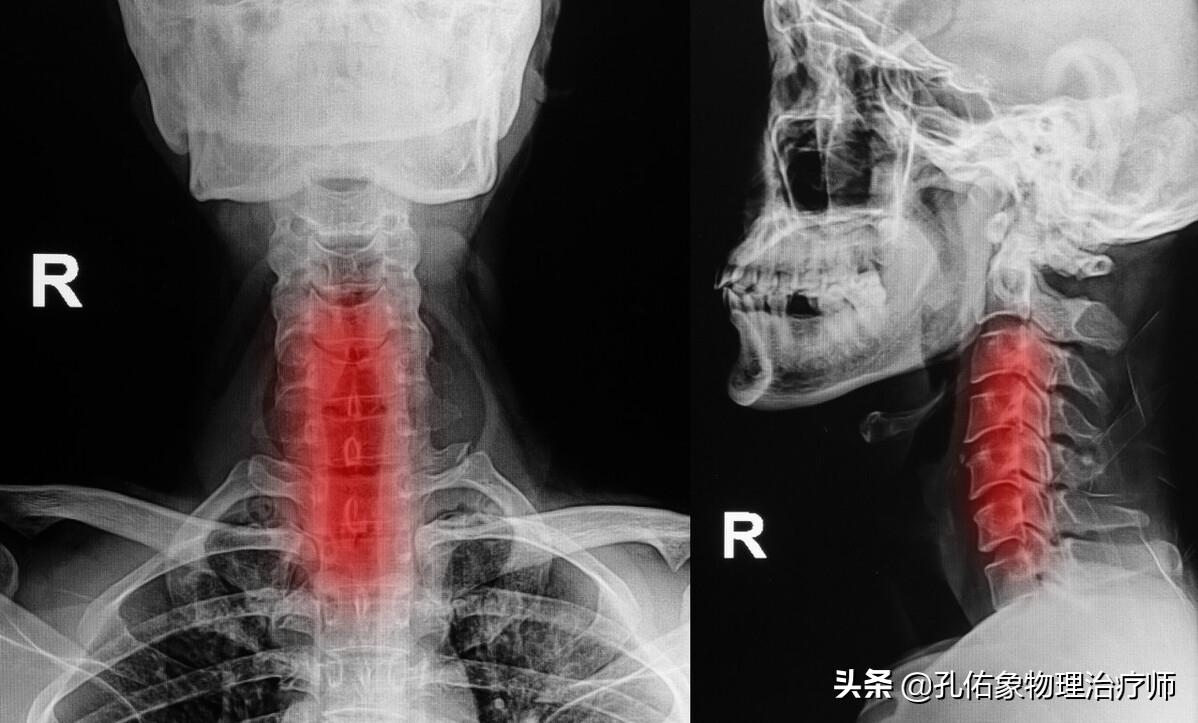

很多颈椎不好的人,会描述自己的手麻、感觉减退,手臂疼痛或是颈椎活动受限等;因为支配我们整个上肢的运动和感觉的神经都是从颈椎发出来的,一旦颈椎出现问题就会卡压神经而产生症状。

- 颈椎和神经之间有着什么样的关系?

我们人体的颈椎骨头有7节,而颈椎神经却有8对;而这8对颈神经从相应的颈椎的椎间孔穿出。具体来看它们之间的关系:

头颅和第1颈椎之间穿出颈1神经;第1颈椎和第2颈椎之间穿出颈2神经;第2颈椎和第3颈椎之间穿出颈3神经;第3颈椎和第4颈椎之间穿出颈4神经;第4颈椎和第5颈椎之间穿出颈5神经;第5颈椎和第6颈椎之间穿出颈6神经;第6颈椎和第7颈椎之间穿出颈7神经;第7颈椎和第1胸椎之间穿出颈8神经。

神经从椎间孔穿出后,会经过不同的位置,如下图所示:

上图所示的上节段椎体的下关节突和下节段椎体的上关节突形成小关节,当我们头颈运动时,主要依靠小关节打开、关闭、侧移。

可以想一想,您手中的报告单,颈椎退变、骨质增生、生理曲度变化,真正反应的问题是不是就在小关节的变化。

所以,当出现手麻、手臂疼痛或是头颈部活动受限时,务必得考虑小关节的变化,而不是一位想着椎间盘的突出。并且更有必要熟知,您目前存在的症状与片子描述的节段是否吻合?